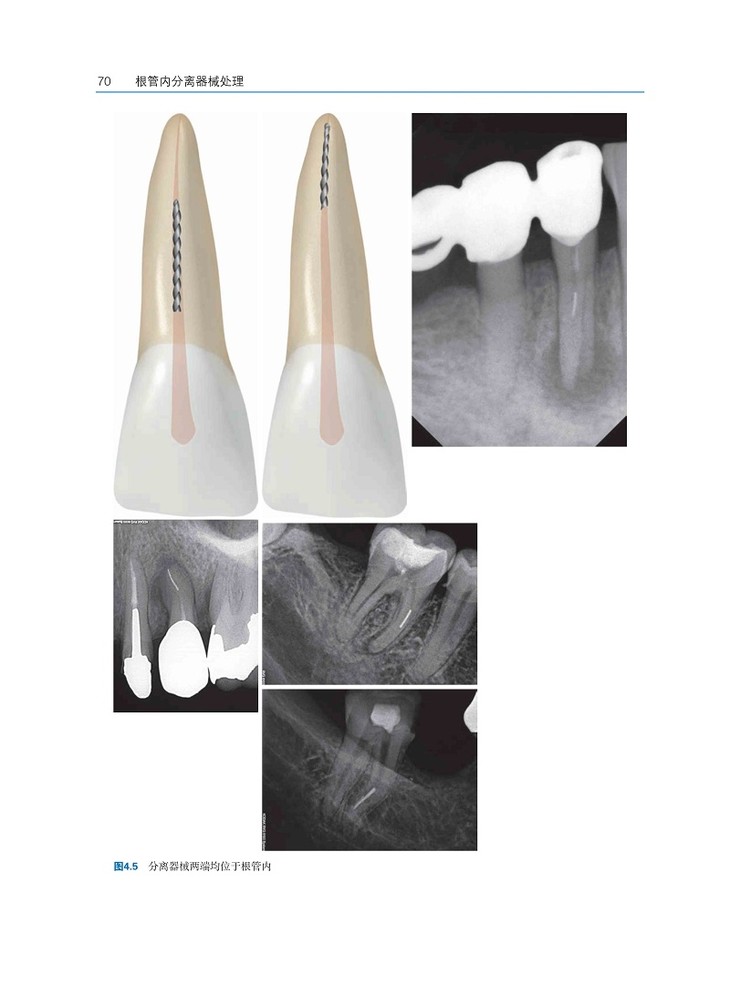

根管治疗中的断械是所有口腔临床医生的噩梦,即便是最有经验的临床医生也无法避免。

遗留在根管内的器械影响了根管的 清理和消毒,继而可能影响根管治疗的预后,还会造成患者的心理负担,甚至引起医疗纠纷。